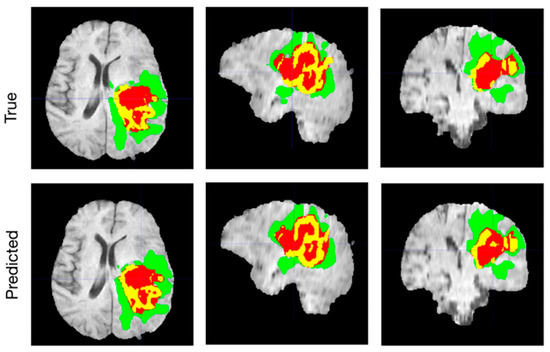

4. Experimental Results